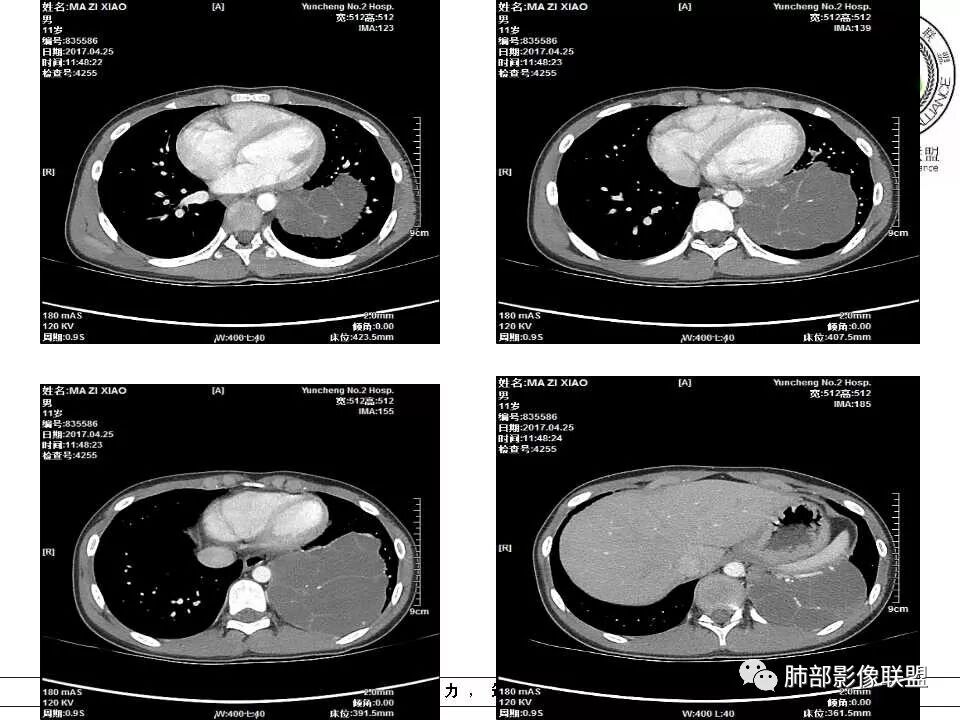

病例提供:运城市第二医院  王崇军

左下肺囊性占位,多发分隔,增强分隔及边缘强化,腹主动脉供血,考虑肺隔离征。

儿童左下肺囊性占位,多发分隔,增强分隔可见强化,腹主动脉供血,肺隔离征。

左肺下叶病灶,囊性为主,内见分隔,边界清晰,首先考虑良性病变,增强可见体循环供血,考虑肺隔离症

左下肺囊性团块灶,多发分隔,增强分隔及边缘强化,主动脉供血,考虑肺隔离症,叶外型。

左肺下叶多房囊性病灶,主动脉分支供血,肺静脉回流,符合肺段隔离症,应该是肺外型吧

左肺下叶囊性变,可见多发分隔,增强后分隔及边缘可见强化,并可见降主动脉分支进入,考虑叶外型肺隔离症

左下肺肿块,内部见多分隔,囊性密度,增强见腹主动脉分支、肺动脉供血,考虑肺隔离症,鉴别支气管囊肿

儿童,左下肺多房囊性占位,增强分隔强化,腹主动脉供血,肺隔离征。

电话随访,患者在西安某医院手术,为肺隔离症,供血两支动脉,均来自腹主动脉,引流入肺静脉。